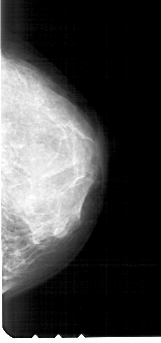

A_1721_1.RIGHT_MLO

RIGHT_MLO LINES 5431 PIXELS_PER_LINE 2566 BITS_PER_PIXEL 12 RESOLUTION 43.5 NON_OVERLAY